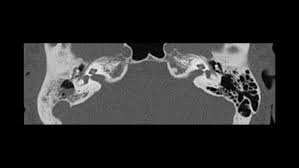

Chronic suppurative otitis media is persistent inflammation of the middle ear or mastoid cavity. Chronic suppurative otitis media (csom) is one of the most common childhood diseases worldwide, and according to the world health organization (who), it affects anywhere between 65 and 330 million people worldwide, but mainly in the developing countries 1, 2, 3 . Complications include development of aural polyps, cholesteatoma, and other infections. Chronic suppurative otitis media (csom) is a chronic inflammation of the middle ear and mastoid cavity that is characterised by discharge from the middle ear through a perforated tympanic membrane for at least 6 weeks. Chronic suppurative otitis media (csom) is a chronic infection of the middle ear cleft (including eustachian tube, middle ear, and mastoid) that is defined by three elements:

1) perforation of the tympanic membrane due to acute infection or tympanotomy tube, 2) discharge from the middle ear (otorrhea), and 3) prolonged duration (;gt;2 wk). Chronic suppurative otitis media is persistent inflammation of the middle ear or mastoid cavity. Chronic suppurative otitis media dr. Chronic suppurative otitis media (csom) is one of the leading causes of preventable disabling hearing impairment (dhi) in developing countries. Chronic suppurative otitis media is a serious disease with a bacterial infection in the middle ear. Acute otitis media and blockage of a eustachian tube are among the causes of chronic suppurative otitis media. Chronic suppurative otitis media (csom) is a common cause of hearing impairment and disability. 1, 2, 3 chronic suppuration can occur. Csom is assumed to be a complication of acute otitis media (aom). The principal causative organisms are pseudomonas aeruginosa, proteus sp, staphylococcus, other gram negative and anaerobic bacteria. 13 to meet the requirement for chronic, the. Like csom, ome often occurs after acute otitis media (aom) … Chronic suppurative otitis media (csom) is a chronic infection of the middle ear cleft (including eustachian tube, middle ear, and mastoid) that is defined by three elements:

Chronic suppurative otitis media (csom) is one of the leading causes of preventable disabling hearing impairment (dhi) in developing countries. It is characterized by chronic drainage from the middle ear associated with tympanic membrane (tm. Acute otitis media and blockage of a eustachian tube are among the causes of chronic suppurative otitis media. Complications include development of aural polyps, cholesteatoma, and other infections. There will be a purulent discharge through a perforated tympanic membrane present for more than 6 weeks, conductive hearing loss and often, inflammation of the mastoid cavity. Chronic suppurative otitis media (csom): 1) perforation of the tympanic membrane due to acute infection or tympanotomy tube, 2) discharge from the middle ear (otorrhea), and 3) prolonged duration (;gt;2 wk). Csom occurs following an upper respiratory tract infection that has led to acute otitis media.